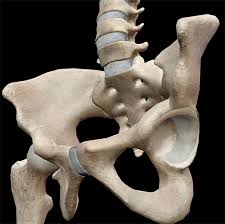

Each innominate bone is composed of three parts, which fuse at the acetabulum. Mri of the female pelvis: This study gives results of magnetic resonance imaging (mri) in the evaluation of male (23 cases) and female (29 cases) pelvis. Anatomical structures of the abdomen. Designed to help you quickly learn or review normal anatomy and confirm variants, imaging anatomy: One major similarity is the four chambered heart. Anatomy by dr abdullah hajar; If you want to learn how to read ct scans of the abdomen and pelvis proficiently, this video is an excellent starting point. The pelvis is firmly attached to the spine (sacroiliac joint) and the limb is longer and more angulated than the thoracic limb (which is designed to bear weight and absorb impact). The cat has 230 bones, as opposed to 206 within the human body. The pelvic girdle (hip girdle) is formed by a single bone, the hip bone or coxal bone (coxal = hip), which serves as the attachment point for each lower limb. 6.1a, b) is a bony ring consisting of paired innominate bones, the sacrum and coccyx. Chest, abdomen, pelvis provides detailed views of anatomic structures in successive imaging slices in each standard plane of imaging.

The pelvis's frame is made up of the bones of the pelvis, which connect the axial skeleton to the femurs, and therefore acts in weight bearing of the upper body.

The pelvic girdle (hip girdle) is formed by a single bone, the hip bone or coxal bone (coxal = hip), which serves as the attachment point for each lower limb. The labeled structures are (excluding the correct side): Page 1 of 15 (wow) bony pelvis anatomy skeletally radiographs ct protocols pelvic ring fx sacrum Both cats and humans have this very sophisticated heart design. Tanksi and jordan ruby the rich vascular supply of the pelvis not only supports the structures contained within it, including the bladder, rectum, and reproductive organs, but also extends to the lower extremities. This study gives results of magnetic resonance imaging (mri) in the evaluation of male (23 cases) and female (29 cases) pelvis. Browse 500 sets of cat anatomy pelvic flashcards. Posted by radiologypics ⋅ march 21, 2013 ⋅ 1 comment. Anatomy of the cat (pelvic limb) origin of sartorius. Mri of the female pelvis: The slice thickness is 2.5 mm. Khati, andres krauthamer, venkatesh krishnasamy, emily j. Ct abdomen and pelvis coronal anatomy in the male.